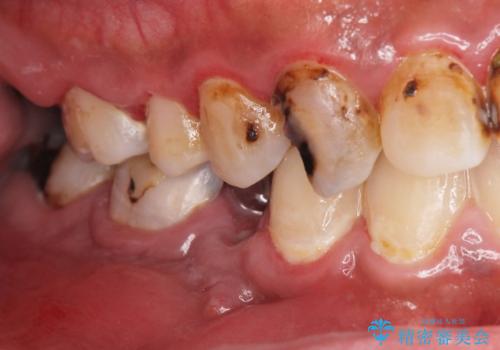

まず徹底的に虫歯を取り除き、保存が出来ない部位は抜歯(親知らずを含む)を行い、根管治療が必要な部位は精密根管治療を行いました。

また、虫歯が歯肉の中まである場合はAPF(歯肉弁根尖側移動術)も行なっています。